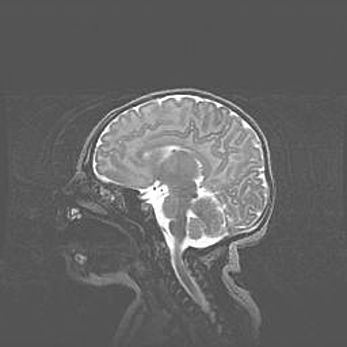

Мальформация Денди-Уокера. Киста задней черепной ямки.

Агенезия мозолистого тела.

Возраст: 2,5 месяца

Вес: 2420 г

Пол: женский

Окружность головы: 37 см

Срок гестации: 32 недели

Мальформация Денди—Уокера — редкий вид патологии ЦНС, представляющий собой врожденный порок развития каудального отдела ствола и червя мозжечка, ведущий к неполному раскрытию срединной (Мажанди) и латеральных (Лушка) апертур IV желудочка мозга. Для этогно синдрома характерна триада симптомов: гипотрофия червя мозжечка и/или полушарий мозжечка, кисты задней черепной ямки, гидроцефалия различной степени. В 70% случаев порок сочетается и с другими аномалиями головного мозга, в частности с агенезией мозолистого тела.